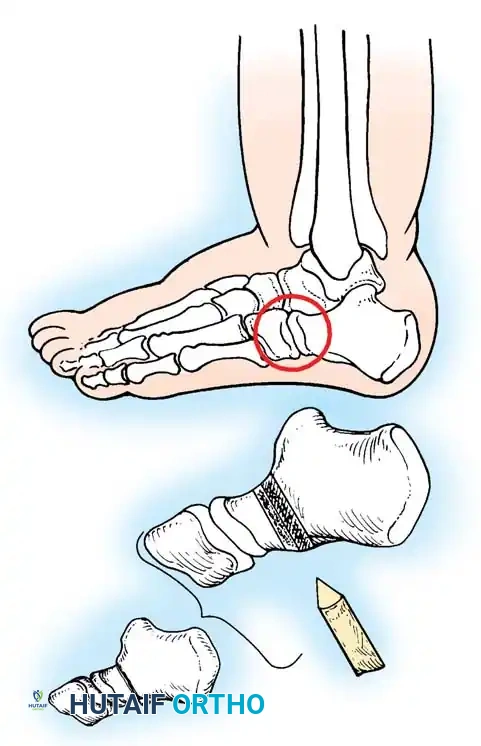

McHale Procedure (Medial Cuneiform Opening Wedge and Cuboid Closing Wedge)

For residual "bean-shaped" foot deformities characterized by severe midfoot adductus:

1. Lateral Incision: A closing wedge osteotomy of the cuboid is performed to shorten the lateral column.

2. Medial Incision: An opening wedge osteotomy of the medial cuneiform is performed.

3. Graft Transfer: The bony wedge excised from the cuboid is meticulously shaped and impacted into the medial cuneiform osteotomy to lengthen the medial column.

4. Fixation: Both osteotomies are stabilized with K-wires.

Image

Fig. 20: Osteotomies of the medial cuneiform and cuboid for correction of residual deformity. (A) Lateral and medial incisions. (B) Removal of dorsolateral wedge from the cuboid. (C) Placement of the wedge into the opening osteotomy of the medial cuneiform.